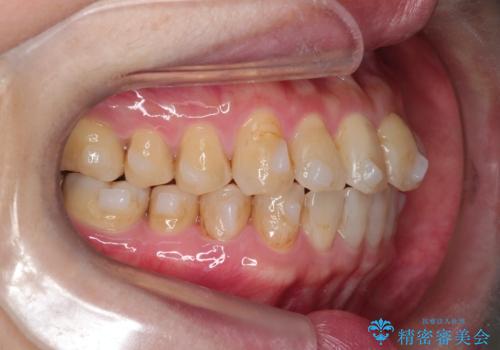

【インビザライン】前歯のガタガタを治したい

- 前歯のガタガタを主訴に来院されました。

上の歯の前突も気になってたため、奥歯の遠心移動も行いながらインビザラインにて治療を行いました。

前歯も下がり満足していただきました。

今回は奥歯の遠心移動とIPRを行って配列しています。